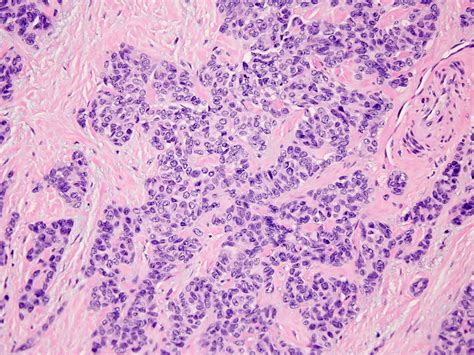

Biopsy is a crucial step in the diagnostic process. A tissue sample is obtained from the tumor and examined under a microscope. The presence of small, round cells and a desmoplastic stroma is indicative of DSRCT. Immunohistochemical staining can also be used to identify specific markers, such as desmin, vimentin, and WT1, which are often expressed in DSRCT.